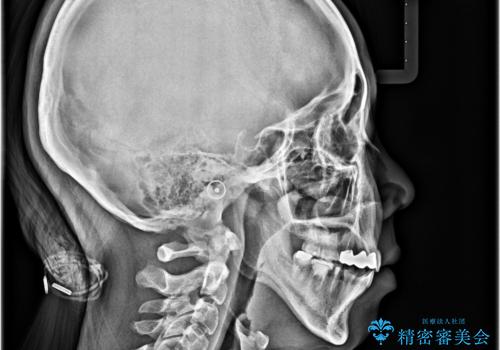

結果として下顎の小臼歯は抜歯せず、右上の抜歯スペースはむし歯処置を兼ねてオールセラミックブリッジにて補綴治療を行うこととしました。

動かない歯での停滞や、出産と子育てなどにより治療期間は長期化しましたが、整った歯列にて仕上げることができました。